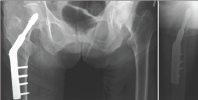

Dynamic hip screw or sliding screw fixation consists of a lag screw, a side plate and cortical screws which fix the side plate to the proximal femoral shaft. The lag screw is inserted into the head of femur from the lateral aspect. For this surgery a C-arm image intensifier is required. The size of the hip is measured pre- operatively on the X-ray to get an idea about the probable size. The patient is supine on the fracture table with feet padded and placed firmly in the table boots. Contra lateral leg is either dropped down or abducted and flexed in a thigh holder. After preparation of the patient, the proximal femur is exposed using a lateral incision extending from the greater trochanter to 8-10cm distally. After bone exposure the guide wire is drilled into the proximal femur in ideally a centre-centre position and is measured. Triple reaming is done and the screw is inserted and a plate is applied to it which is secured with cortical screws (Figure 2). The idea behind the dynamic compression is that the femoral head component is allowed to move along one place and since bone responds to dynamic stress, the femur may undergo primary healing resulting in joint requiring no remodeling (Figure 3).

Figure 2: An illustration of Dynamic Hip Screw implant in the proximal femur.

Figure 3: Xray Pelvis Anteroposterior and Lateral views showing a Dynamic Hip Screw Implant in the right proximal femur.